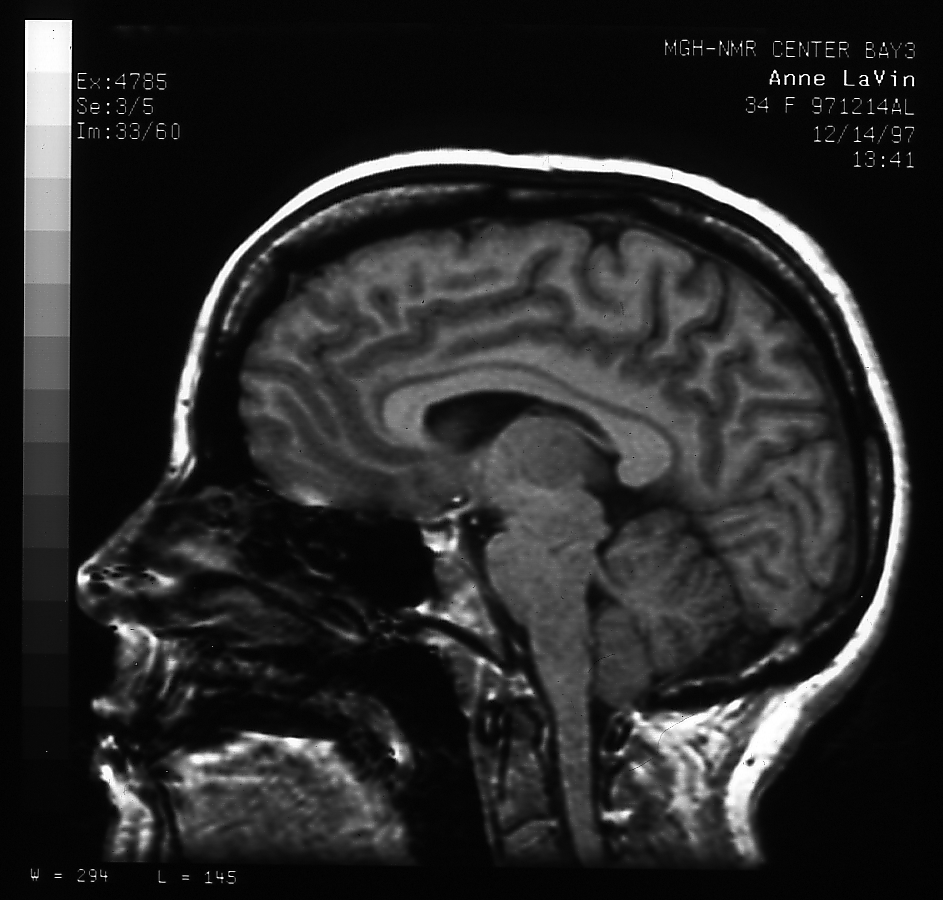

Anne's Brain

MRI picture of Anne's brain

Yep, I've got one.

And that is a scan of it taken with an MRI system. (That's "Magnetic Resonance Imaging" previously known as "Nuclear Magnetic Resonance" imaging, until the "nuclear" scared people and they changed it.) Never fear, I was just an experimental subject, we weren't hunting for anything in particular! I made a two other versions, one 600x573 pixels (233K) for moderate detail, and one 943x900 pixels (568K) if you want to see everything!